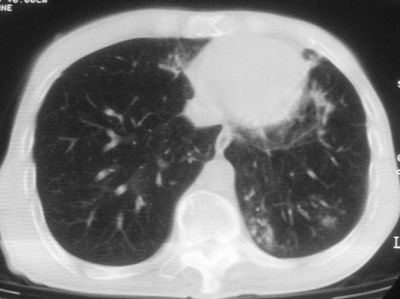

标题: CT11864:男,47岁,反复咳嗽、咯痰、咯血3年,请分析. [打印本页]

标题: CT11864:男,47岁,反复咳嗽、咯痰、咯血3年,请分析.

患者,男,47岁,反复咳嗽、咯痰、咯血3年,再发5天。痰培养未找到真菌、抗酸杆菌、癌细胞。

左肺上叶体积明显缩小,其内见多发透光区,纵隔向左侧移位,左肺下叶多发班片状病灶,边界模糊,1左肺上叶先天肺发育不全,2左肺下叶肺炎,

左肺上叶结核伴肺纤维化,纵隔移位,左肺下叶感染性病变,建议抗炎抗结核后复查,双肺气肿.

1.左肺上叶慢纤空2.左肺下叶炎症

考虑:左肺慢纤伴霉菌球形成、双肺全小叶型肺气肿。

1)考虑为:左肺上叶肺结核(空洞形成),伴左下肺感染;不排除霉菌感染可能。2)肺气肿。

左肺上叶结核伴肺纤维化空洞形成并左肺下叶感染,纵隔牵拉移位,建议作进一步检查排除左侧肺霉菌感染可能。

左上肺发育不良并支扩,慢支肺气肿并感染。